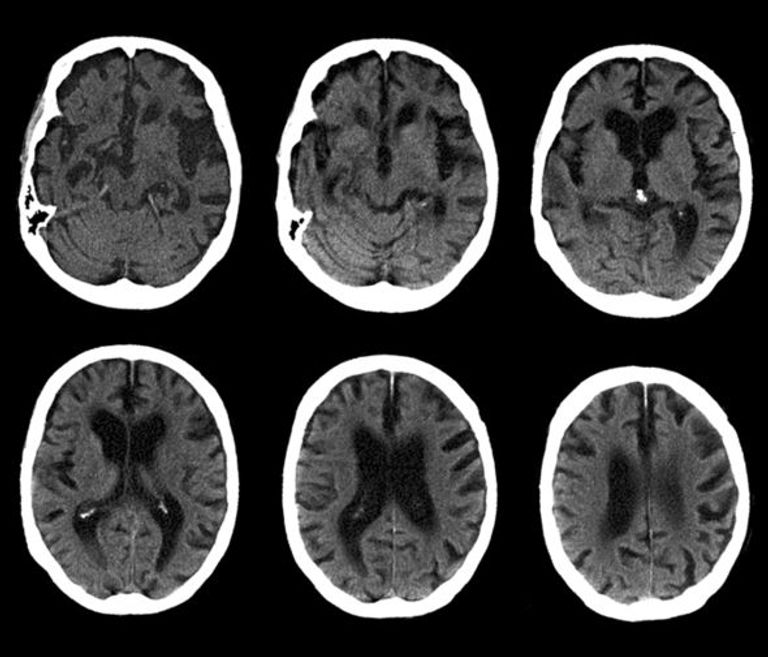

وأشارت الدراسة، إلى وجود نوعين للخرف، يتمثل الأول في الخرف اللفظي والثاني الخرف الجبهي الصدغي، وهو أحد أنواع الخرف النادرة الذي يصيب منطقة من الدماغ المسؤولة عن التصرفات والشخصية.

ويعاني المصابون به من أعراض عدة منها ضعف الوعي واللامبالاة وفقدان المهارات الشخصية والقدرة على التحكم بتصرفاتهم.